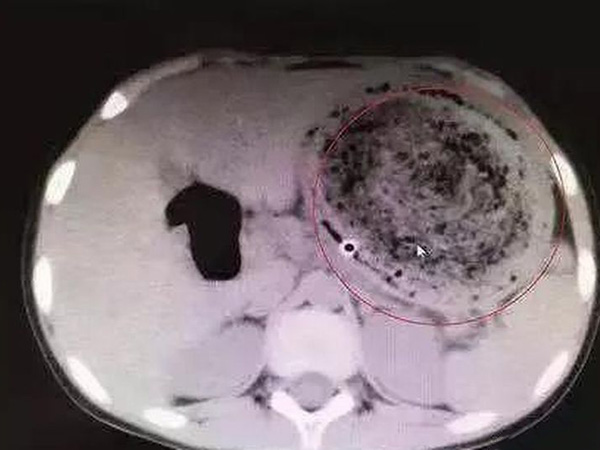

ಎಂಟು ವರ್ಷದ ಬಾಲಕಿಯ ಹೊಟ್ಟೆಯಲ್ಲಿತ್ತು 'ಕೂದಲಿನ ದೊಡ್ಡ ಉಂಡೆ'! ವೈದ್ಯರೇ ನೋಡಿ ಶಾಕ್ ಆದರು!!

ವೈದ್ಯರು ಆಕೆಯ ಮೇಲೆ ಗ್ಯಾಸ್ಟ್ರಿಕ್ ಲ್ಯಾವೆಜ್ ಚಿಕಿತ್ಸೆ ಮಾಡಿದರು. ಈ ವಿಧಾನದಿಂದ ಹೊಟ್ಟೆಯನ್ನು ಸಂಪೂರ್ಣವಾಗಿ ಖಾಲಿ ಮಾಡಲಾಗುತ್ತದೆ. ಆದರೆ ಬಾಲಕಿಯ ಹೊಟ್ಟೆಯಲ್ಲಿ ಕೂದಲಿನ ದೊಡ್ಡ ಉಂಡೆಯು ಇರುವುದನ್ನು ನೋಡಿದ ವೈದ್ಯರು ಅಚ್ಚರಿಗೊಳಗಾದರು.

ಬಾಲಕಿಗೆ ತಕ್ಷಣ ಶಸ್ತ್ರಚಿಕಿತ್ಸೆ ಮಾಡಿ ಆಕೆಯ ಹೊಟ್ಟೆಯಲ್ಲಿ ಇದ್ದಂತಹ ಕೂದಲಿನ ಉಂಡೆಯನ್ನು ಹೊರಗೆ ತೆಗೆಯಲಾಯಿತು.